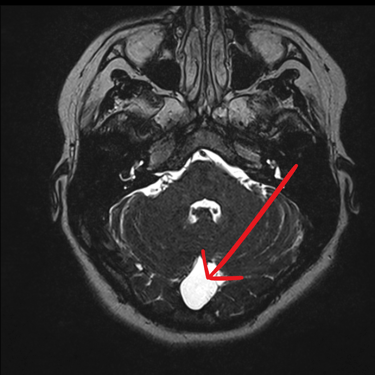

El quiste aracnoideo suboccipital es una lesión benigna de origen congénito, formada por una acumulación de líquido cefalorraquídeo entre las membranas aracnoideas. Aunque en muchos casos puede ser asintomático y detectarse de manera incidental, también puede producir cefalea, mareos, alteraciones del equilibrio o compresión del cerebelo y tronco encefálico. La resonancia magnética (RMN) es el estudio de elección, ya que permite definir la localización, tamaño y sus efectos sobre estructuras adyacentes. Este diagnóstico es clave para establecer la conducta terapéutica, que puede variar entre seguimiento clínico-radiológico o tratamiento quirúrgico en casos sintomáticos o de crecimiento progresivo.